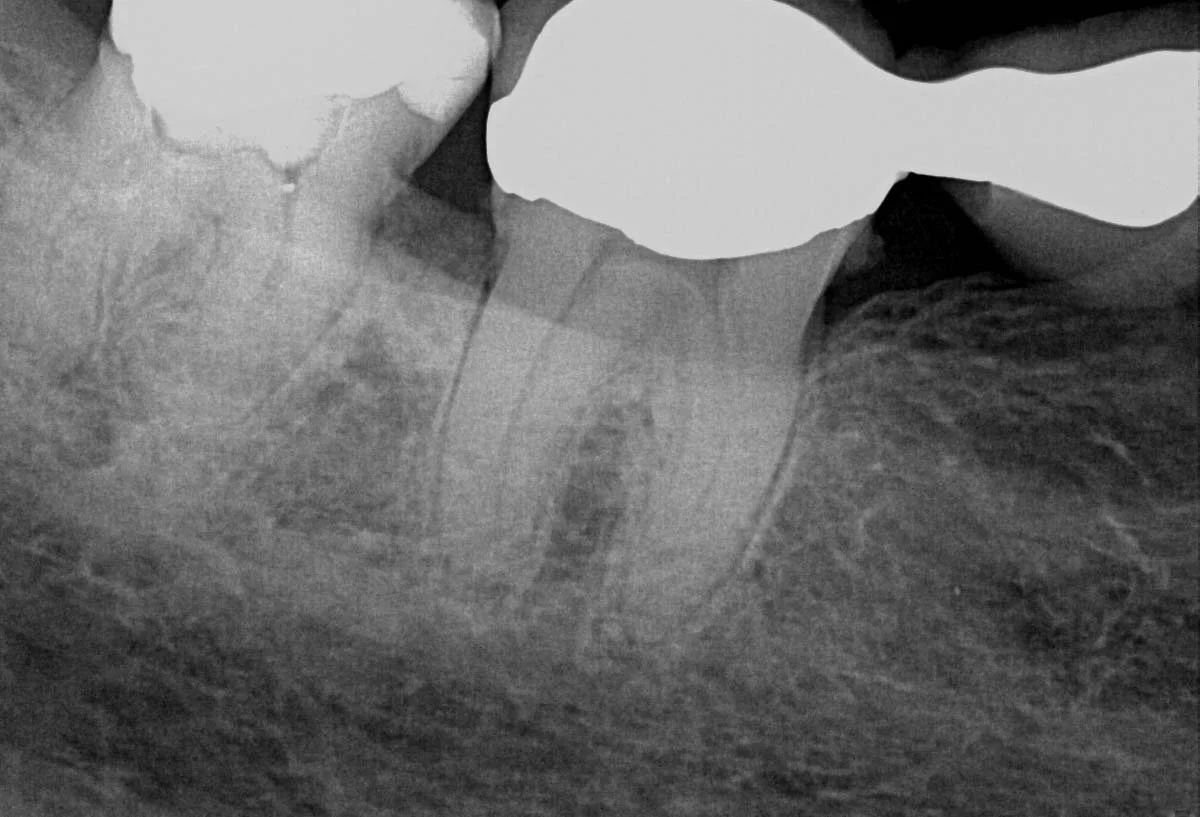

This healthy 71 year old female patient presented with an unrestorable right mandibular posterior four unit bridge, due to catastrophic fracture of the mesial retaining tooth 44.

Due to the extent of the infection, tooth 44 was extracted, the site carefully curetted, and then left to heal for three months prior to bone volume assessment with a cone beam tomograph (Soridex).